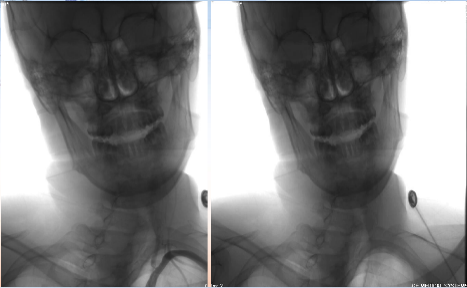

过程影像

病历夹什么径技·第152期|串联营病历夹:川陕大营_https://www.jmylbn.com_新闻资讯_第83张

病历夹什么径技·第152期|串联营病历夹:川陕大营_https://www.jmylbn.com_新闻资讯_第84张

<<滑动查看下一张图片>>

病历夹什么径技·第152期|串联营病历夹:川陕大营_https://www.jmylbn.com_新闻资讯_第85张

病历夹什么径技·第152期|串联营病历夹:川陕大营_https://www.jmylbn.com_新闻资讯_第86张

病历夹什么径技·第152期|串联营病历夹:川陕大营_https://www.jmylbn.com_新闻资讯_第87张

对侧造影显示,右侧大脑前动脉供血区血流较好。

病历夹什么径技·第152期|串联营病历夹:川陕大营_https://www.jmylbn.com_新闻资讯_第88张

接下来处理远端,Synchro微导丝与Rebar微导管的辅助下,选择置入Solitaire(4-20)支架,支架打开后使用抽拉结合的方式使血管再通。

病历夹什么径技·第152期|串联营病历夹:川陕大营_https://www.jmylbn.com_新闻资讯_第89张

取栓后造影如下:

手术评估

病历夹什么径技·第152期|串联营病历夹:川陕大营_https://www.jmylbn.com_新闻资讯_第90张

病历夹什么径技·第152期|串联营病历夹:川陕大营_https://www.jmylbn.com_新闻资讯_第91张

病历夹什么径技·第152期|串联营病历夹:川陕大营_https://www.jmylbn.com_新闻资讯_第92张